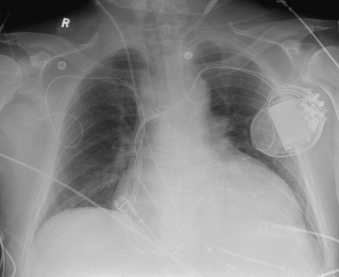

Central Venous Lines ( Figs. 22-1 to 22-13 )

To avoid mechanical irritation (from the catheter tip) and chemical irritation (from infusate) of the right atrium, the catheter tip of a central venous line should be further than the junction of the internal jugular vein and subclavian veins (near the level of the first thoracic rib). In addition, the tip should not be further in than the junction of the superior vena cava and right atrium. Central venous catheters that are intended to record central venous pressure should lie distal to the last venous valves (in the subclavian and internal jugular veins, 2.5 cm proximal to the beginning of the brachiocephalic vein) and before the right atrium. The ideal position of the tip of a peripherally inserted central catheter (PICC) line is in the distal superior vena cava.